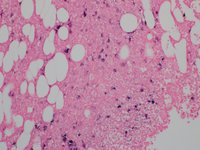

Lymphoplasmacytic Lymphoma CD138

Category: Lymphoma: Mature B-cell and Plasma cell Neoplasms > Low-grade B-cell lymphoma > Lymphoplasmacytic lymphoma

CD138 positive plasma cells are arranged singly and in small clusters. The background shows CD138 negative hematopoetic cells.